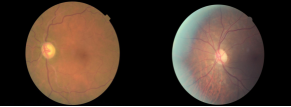

For the OOD detection task, we treat CIFAR 10 and MNIST as the in-distribution datasets, and FashionβMNIST, OMNIGLOT, and SVHN as the OOD datasets. To validate the advantage of BNN encoding on limited observations, we compose a medical image benchmark using samples from the Diabetes Retinopathy Detection (DRD) dataset [8], with samples shown in Figure 3. We treat healthy samples as in-distribution data and unhealthy samples as OOD data. Distinct from the settings in some existing works [27] which include OOD data in the training, we exclude the OOD data when training the feature encoder. We use the AUROC and AUPR as the evaluation metrics for OOD detection tasks, and adopt accuracy and the macro F1-score to evaluate the classification performance. Detailed definitions of the evaluation metrics and further descriptions of the datasets can be found in the appendix.

Diabetes Retinopathy Detection (DRD). For this experiment, we define in-distribution samples as healthy (no DR; with label 0), and OOD samples as DR (mild, moderate, severe, or proliferative DR; corresponding to labels 1β4). We select 50 healthy images to train the encoder, and compute and from these samples using the trained encoder. For testing, we select 50 images as in-distribution data and 50 images as the OOD data. All images are resized to 6464 for computational convenience. We train the encoder with a task to classify whether the input image is the left eye or right eye. The examples of healthy and DR are presented in Figure 8.